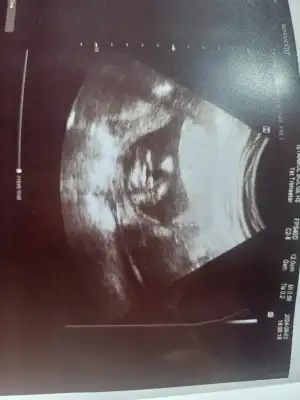

canım erkek annesi olacakmışsın çok sevindim kucağına almakta nasip olur inşallah